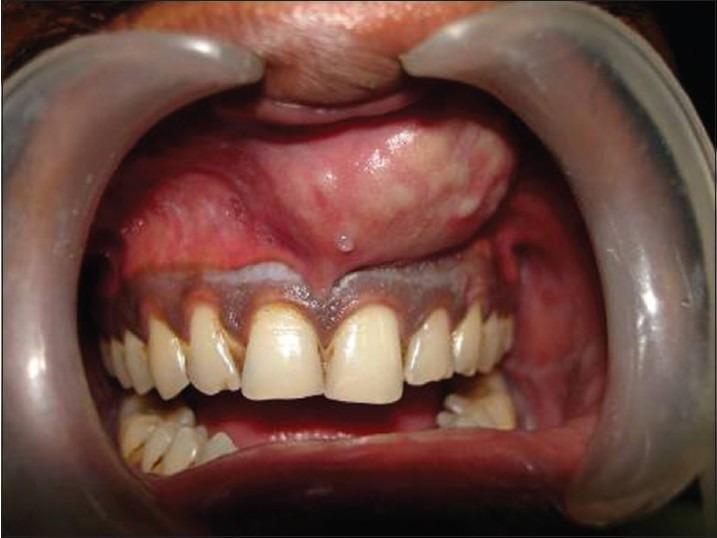

Dentigerous cyst is a developmental odontogenic cyst, which develops due to fluid accumulation between the reduced enamel epithelium and unerupted tooth crown. The condition is frequently seen with the permanent dentition, usually associated with impacted mandibular third molars and maxillary canines. Rarely, dentigerous cyst occurs in association with a supernumerary tooth. Pain, swelling, and facial asymmetry are occasionally seen; however, they are usually asymptomatic and observed during radiographic examination. Early diagnosis and treatment planning entails thorough history taking, clinical and radiographic examination coupled with histopathology. This article reports an unusual occurrence of dentigerous cyst of anterior maxillary region seen with an inverted impacted mesiodens cyst enucleation along with extraction of the mesiodens was carried out and no complications were observed during the follow-up.

摘要

含牙囊肿是一种发育性牙源性囊肿,由于釉质发育不全上皮与未萌出牙冠之间积液而形成。这种情况在恒牙列中较为常见,通常与下颌阻生第三磨牙和上颌尖牙有关。含牙囊肿很少与多生牙同时出现。偶尔会出现疼痛、肿胀和面部不对称;然而,它们通常无症状,在影像学检查时被发现。早期诊断和治疗计划需要全面的病史采集、临床和影像学检查以及组织病理学检查。本文报告了一例上颌前部区域罕见的含牙囊肿病例,该囊肿与倒置阻生正中多生牙囊肿同时存在,对正中多生牙进行了囊肿摘除及拔除,随访期间未观察到并发症。